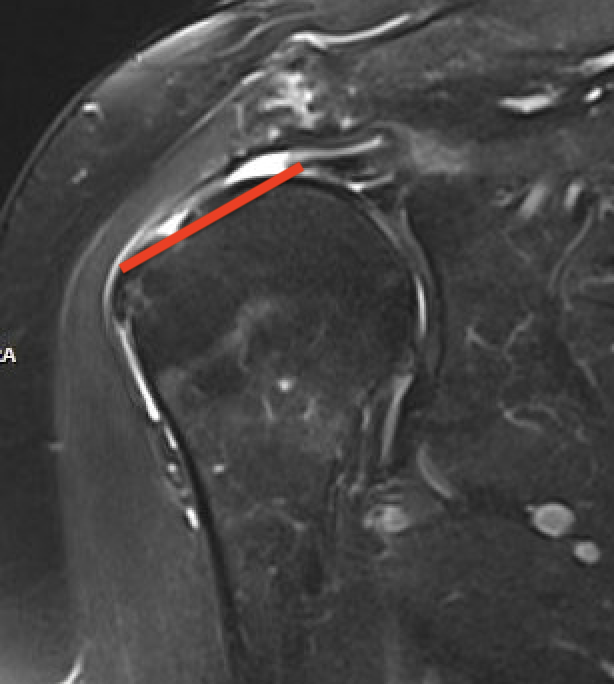

Full thickness rotator cuff tears

Small full thickness rotator cuff tear of supraspinatus - retracted to footprint

Large full thickness tear of supraspinatus and infraspinatus tendon - retracted to midhumeral head

Massive rotator cuff tear of the supraspinatus and infraspinatus tendon - retracted to glenoid

Tangent sign

- sagittal MRI

- line connecting superior coracoid and superior border scapular spine

- if supraspinatus muscle is below line, there is significant atrophy

- positive tangent sign / significant atrophy associated with larger tears / irrepairable tears

Negative tangent / no atrophy Positive tangent / significant supraspinatus atrophy